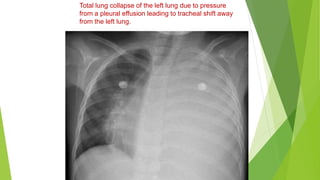

Total lung collapse due to obstructive pathology

causing a white out of the right hemithorax. Note the

trachea is pulled towards the collapsed lung

Total lung collapse of the left lung due to pressure

from a pleural effusion leading to tracheal shift away

from the left lung.